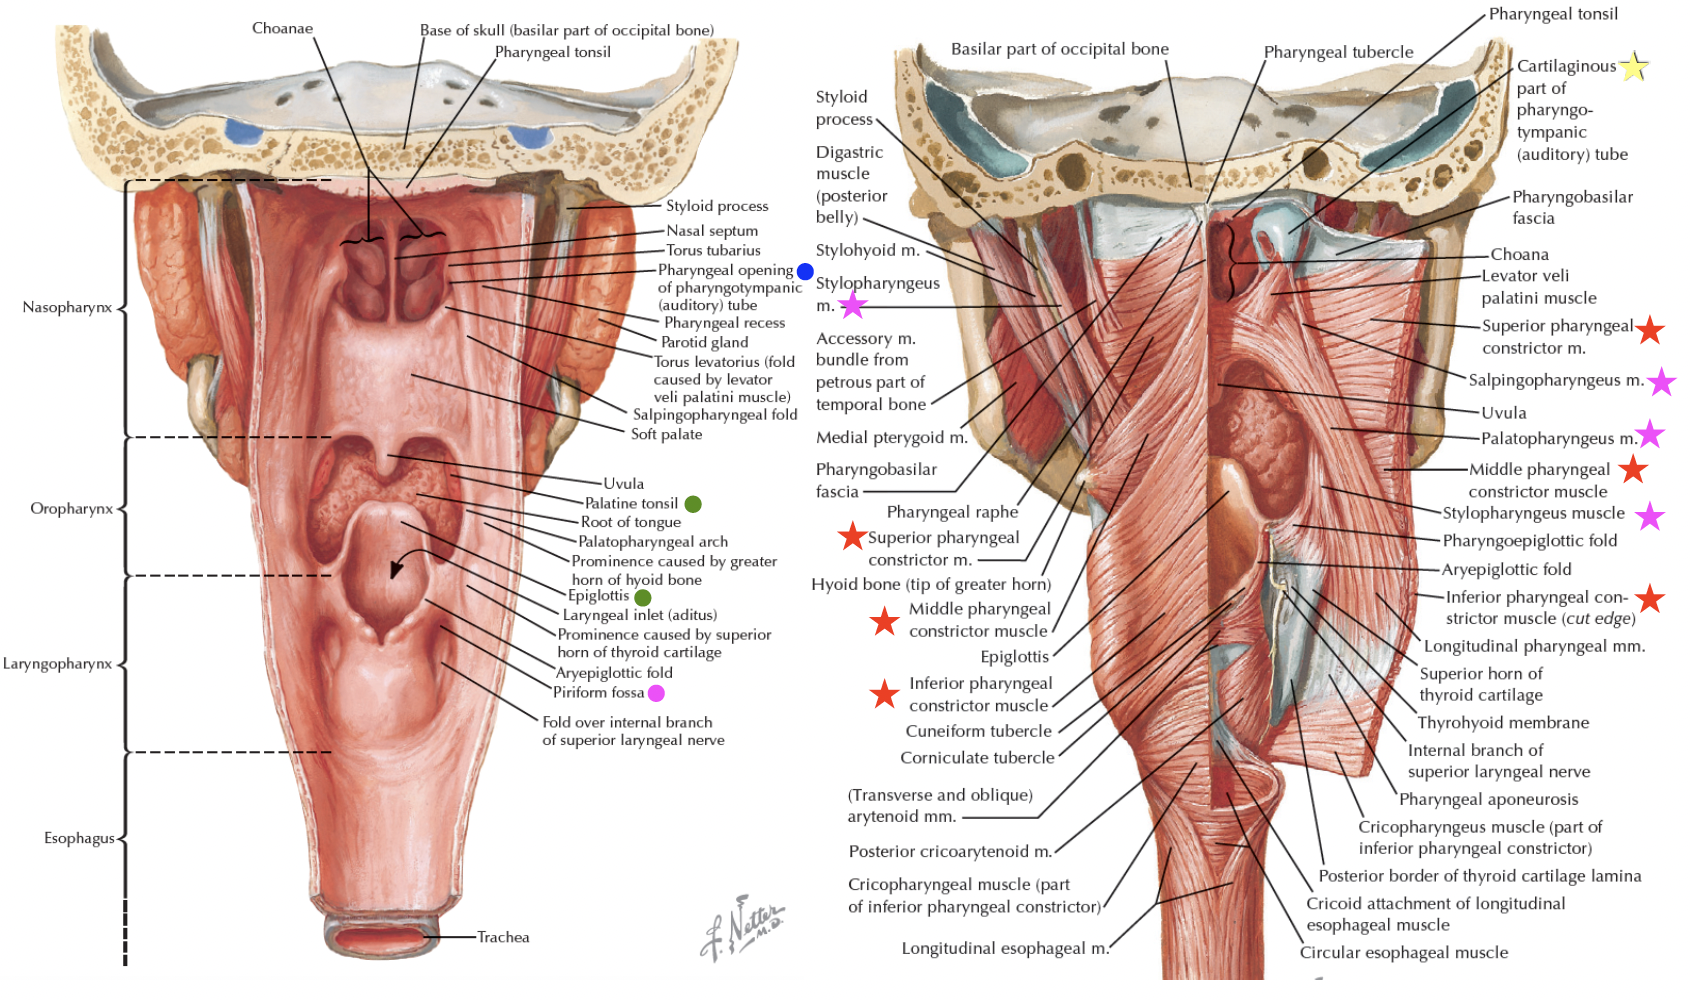

Pharynx

Structure

Nasopharynx

Sensor:CN V

- Opening of Pharyngotympanic tube (auditory tube, Eustachian tube)

- 前:Salpingopalatine fold

- 後:Torus tubarius Salpingopharyngeal fold

- Pharyngeal tonsil

Oropharynx

Sensor:CN IX

由外而內

- Palatoglossal fold(arch)

- Palatine tonsil

- Palatopharyngeal fold(arch)

- 分隔口腔與口咽(fauces)

Laryngopharynx

Sensor:CN X

- Epiglottis

- Choana 後鼻孔

- Piriform recess

- (medial) larynx;

- (lateral) thyroid cartilage

- (posterior) Inf. pharyngeal constrictor m.

Muscle

外部

-

pharyngeal constrictor

- CN X (Pharyngeal plexus) 控制

- 環狀肌肉

外 內 Sup Pterygomandibular raphe pharyngeal raphe Mid Hyoid bone 的 greater horn,

Sup. pharyngeal constrictorInf Thyroid cartilage 的 oblique line,

Cricoid cartilage -

Stylopharyngeus

- 穿入Sup. Mid. pharyngeal constrictor之間

- CN IX 支配

內部

Vagus 支配

- Palatoglossus m

- palatoglossal fold 下

- Palatine aponeurosis lateral side of tongue

- Palatopharyngeus m

- palatopharyngeus fold下

- Hard palate and palatine aponeurosis Thyroid cartilage and pharyngeal wall

- salpingopharyngeus m.會合

- Salpingopharyngeus m.

- salpingopharyngeal fold下

- Cartilage of pharyngotympanic tube(耳咽管軟骨) thyroid cartilage and pharyngeal wall

- Levator veli palatine m.

- From Scaphoid fossa

V3支配

- Tensor veli palatini m.

- 增加軟顎強度

- 打開耳咽管

- 繞過 pterygoid process